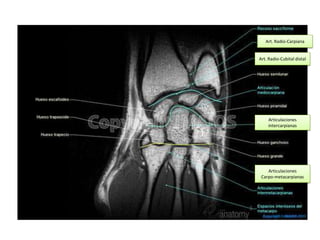

Art. Radio-Carpiana

Art. Radio-Cubital distal

Articulaciones

intercarpianas

Carpo-metacarpianas